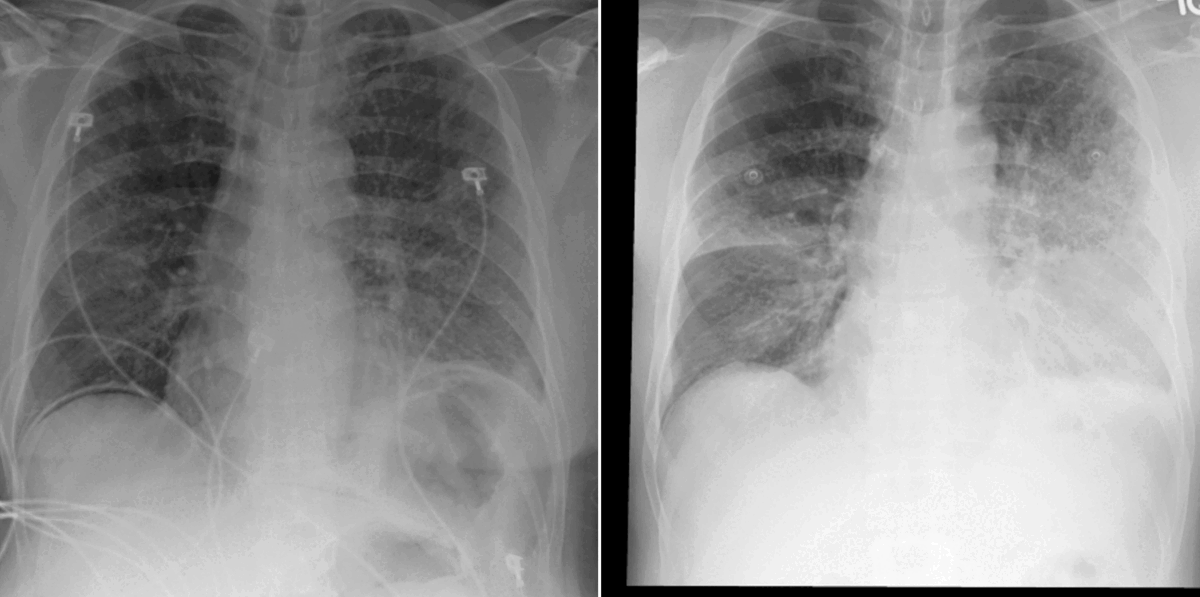

In our work, we found that linking multiple images during pretraining makes for both better language and vision representations, enabling the AI model to better associate information present in both the text and the images. This means that when given a radiology report of a chest x-ray, for example, with the description “increased opacities in the left lower lung compared with prior examination,” a model can more accurately identify, locate, and compare findings, such as opacities. This improved alignment between data modalities is crucial because it allows the model to provide more accurate and relevant insights, such as identifying abnormalities in medical images, generating more accurate diagnostic reports, or tracking the progression of a disease over time.

Through our relationships with practicing radiologists and Nuance, we were able to identify and concentrate on a clinically important research problem, finding that accounting for patient history matters if we want to develop AI solutions with value. To help the research community advance longitudinal analysis, we’ve released a new benchmark dataset. MS-CXR-T (opens in new tab), which was curated by a board-certified radiologist, consists of current-prior image pairs of chest x-rays labeled with a state of progression for the temporal image classification task and pairs of sentences about disease progression that are either contradictory or capture the same assessment but are phrased differently for the sentence similarity task.